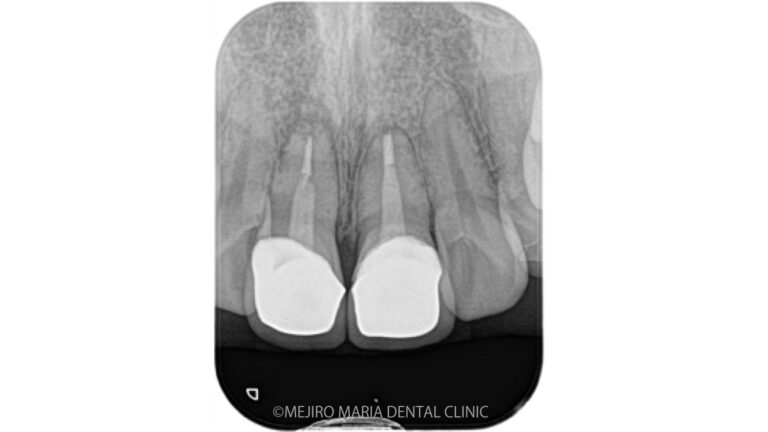

東京 目白マリア歯科 精密根管治療の症例

【生活歯髄保存療法】

神経を残す治療

(回復可能な歯髄炎の場合)

歯髄の細菌感染が少ない初期の不可逆性歯髄炎に対して、炎症がある部分のみ除去して健康な歯髄は保存する治療法です。歯髄を残すため、失敗した場合は歯髄炎の症状が悪化する可能性があり、正確な診断力と技術が必要です。